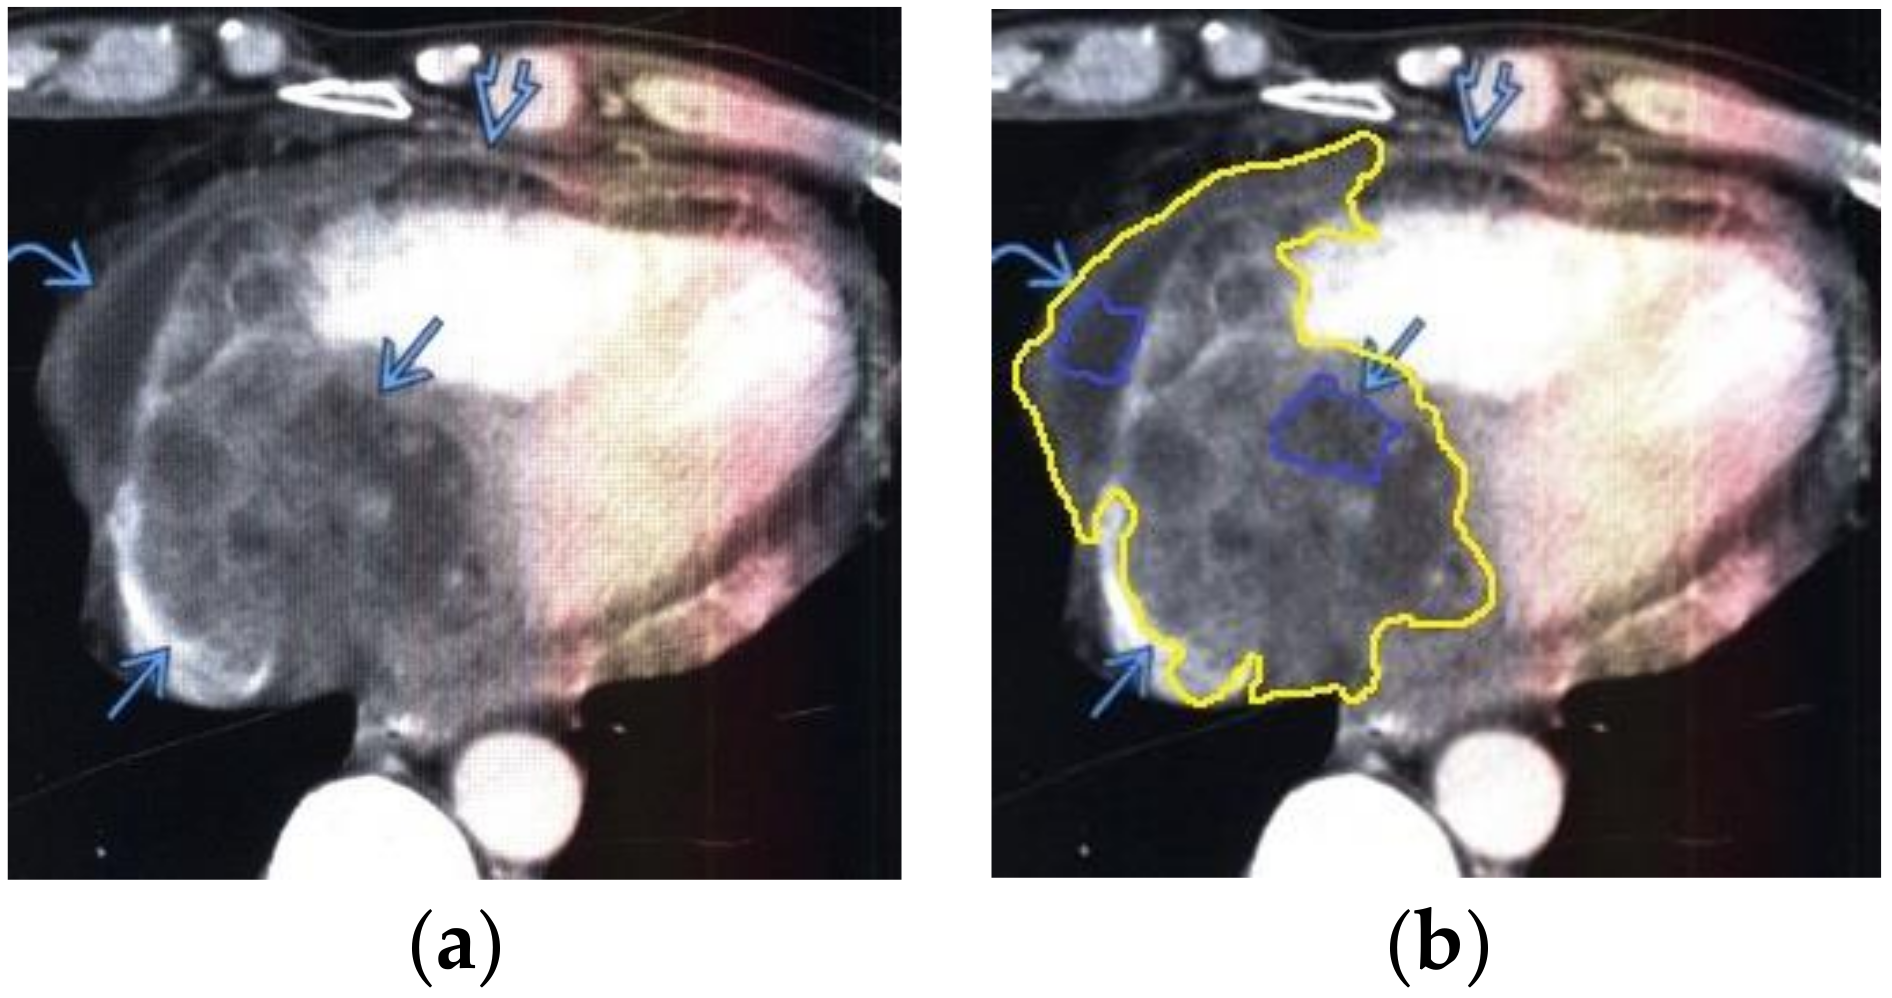

The contour extraction method was used to identify cancerous areas that, after applying the model to eliminate mixed noise, had an increased contrast of volumetric heterogeneous formations in the region of the heart [27]. This method was developed by the authors when analyzing thermal images to assess the condition of the coronary vessels of the myocardium under cardiopulmonary bypass. The contours of the cancerous regions in the examples used for applying the model to eliminate mixed noise (Figure 4, Figure 5, Figure 6, Figure 7, Figure 8 and Figure 9) are highlighted in yellow and they represent the visual boundary of the distribution of volumetric heterogeneous formations.

• For a patient with sarcoma of the heart: during MRI, a volumetric mass was determined in the lateral wall of the right atrium (Figure 7).

Applsci 10 04747 g006

Figure 7. Heart MRI: (a) image with white noise and (b) denoised image with contrast enhancement of sarcoma in the right atrium.

Applsci 10 04747 g007